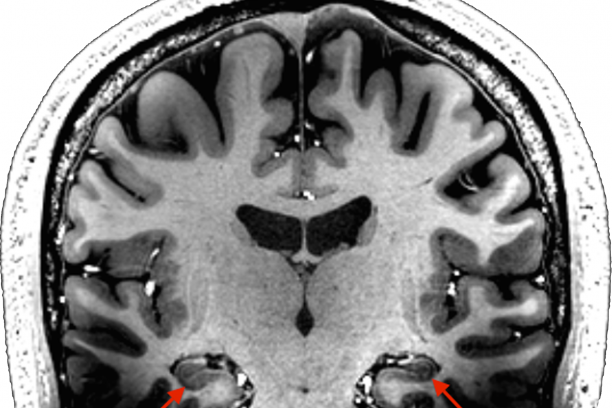

We use magnetic resonance imaging (MRI) to study the brain. MRI machines use magnetic fields to create images of the brain. MRI can be used to obtain very high-resolution images of brain structure. We also use functional MRI to study brain activity. Rather than taking one picture of the brain, with functional MRI we take quick snapshots every few seconds while a person is performing a memory task or even resting quietly. Each snapshot measures brain activity at a given moment. We can put these images together over time to look at changes in brain activity in regions such as the hippocampus. In addition to functional MRI, we collect measures of blood flow and blood volume, which enable us to examine differences in baseline brain activity.

A major focus of the research in our lab is on the hippocampus. The hippocampus is a region of the brain important for learning, memory and emotion. Our work has shown that patients with chronic schizophrenia, but not bipolar disorder with psychosis, have a smaller hippocampus and they don’t use the hippocampus as effectively as healthy people when trying to remember events. We have also found that changes in memory, hippocampal size and function may not be present early in the illness, but instead progress over time. These studies emphasize the importance of studying patients early in psychosis. Our goal is to better understand how memory and the brain change in psychosis over time so that better treatments can be developed.

Based on this work, we have proposed that the main features of psychosis (i.e., delusions and hallucinations) originate from an abnormal interaction between the hippocampus and the cortex. Interactions between the hippocampus and cortex give rise to representations of stimuli, provided either directly by our senses or via imagery and recollection from memory. Such representations provide the basis for conscious awareness of the world and the self. The hippocampus is involved in both binding together and separating stimulus representations from one another. The core deficit of schizophrenia stems from a breakdown in how the hippocampus and cortex communicate to generate these representations. This leads to an impaired ability to classify stimulus representations as internally or externally generated (hallucinations) and to an association of stimulus features with each other, even in the absence of a true relationship (delusions).